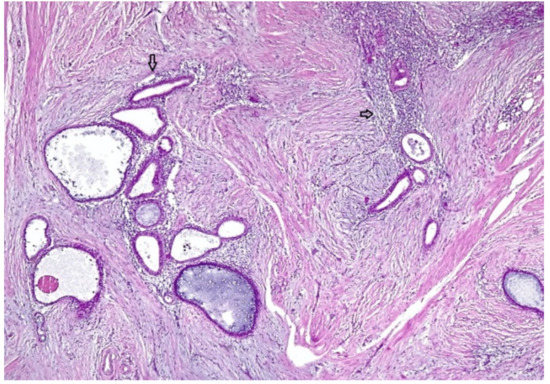

2.2. Case 2